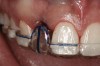

Figure 10  Clinical examination of the bound edentulous space: Measurement of the distal (Fig 10) and mesial (Fig 11) interproximal tissue height using a periodontal probe supplements data obtained from the periapical radiograph. Estimation of the buccal tissue thickness (bone sounding) is performed at the determined location of the gingival zenith using a guide developed from the diagnostic waxing (Fig 12).

Figure 11   Clinical examination of the bound edentulous space: Measurement of the distal (Fig 10) and mesial (Fig 11) interproximal tissue height using a periodontal probe supplements data obtained from the periapical radiograph. Estimation of the buccal tissue thickness (bone sounding) is performed at the determined location of the gingival zenith using a guide developed from the diagnostic waxing (Fig 12).

Figure 11